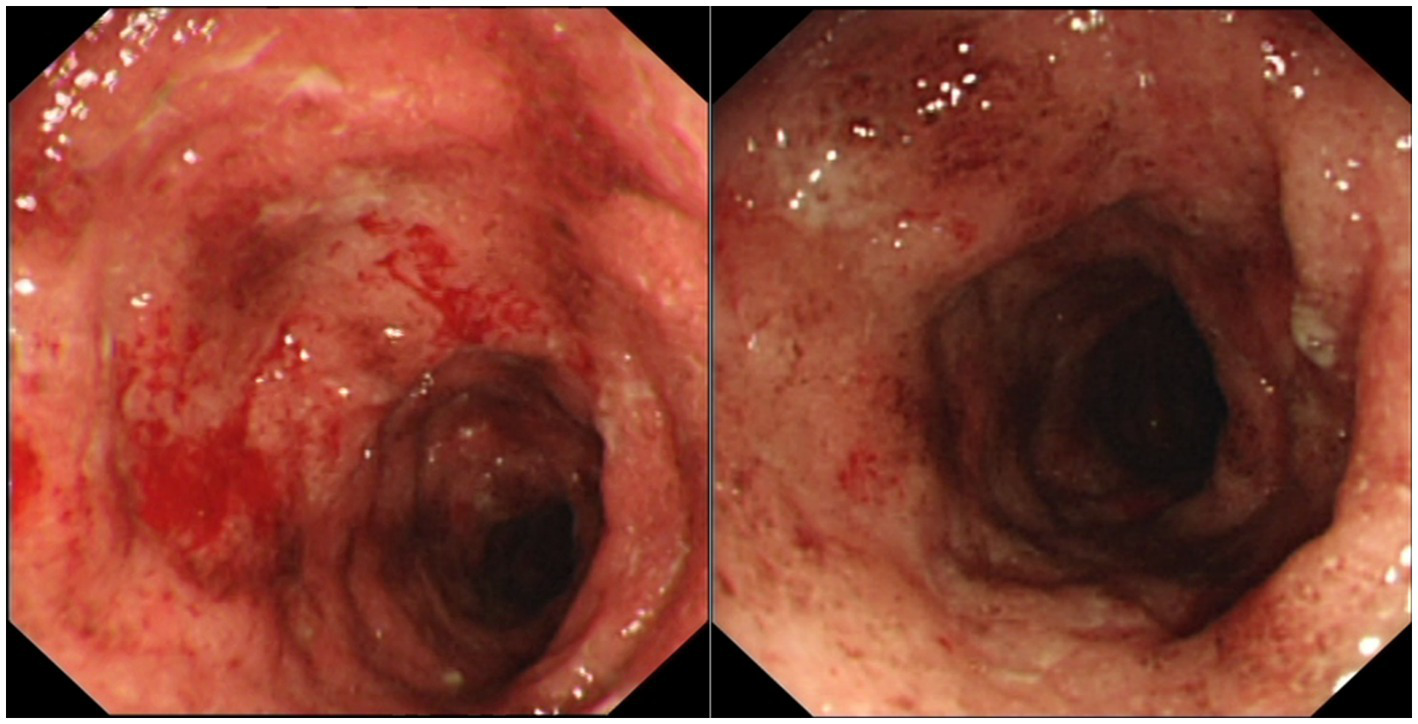

Figure 1

Colonoscopic images showing erythema and granularity of the examined colon mucosa with superficial exudated ulcerations, loss of normal vascular pattern and areas of spontaneous bleeding (Mayo Endoscopy Subscore 3).

A 33-year-old-male, with no known comorbidities, presented to the emergency department on March 2022 with a two-day history of upper abdominal pain radiating to the back, nausea, and vomiting. He also complained of persistent diarrhea for the previous 2 months, with bloody stools for the previous two to 3 weeks. His diarrhea began soon after recovering from a mild COVID-19 infection in January 2022. He had 2 doses of Sinopharm® vaccine in late 2020 and a single dose of the Pfizer® vaccine in November 2021. He had received a short course of metronidazole 500 mg t.i.d 2 weeks prior with no obvious benefit. On examination, the patient appeared distressed, with a temperature of 37.1°C, pulse rate of 102 beats per minute, blood pressure of 117/77 mmHg, respiratory rate of 18 breaths per minute, and oxygen saturation of 96% on room air. His body mass index was 26.5 kg/m2. Initial blood results (summarized in Table 1) were significant for markedly elevated serum amylase, lipase, and CRP, with moderate elevation in ALT and AST (GGT and ALP were normal). Serum lipid profile and electrolytes were normal. CT scan of the abdomen without contrast showed peripancreatic fat stranding suggestive of early acute pancreatitis, mesenteric hyperemia, and multiple millimetric mesenteric lymph nodes. The patient did not give a history of alcohol consumption. His SARS-CoV-2 PCR test from a nasopharyngeal swab was negative. He was promptly hospitalized with a diagnosis of acute pancreatitis and for further investigation of chronic diarrhea with suspicion of UC. Ranson’s score on admission was “0.” He was kept on nil by mouth order and started on aggressive intravenous fluids with analgesia. Fecal calprotectin was markedly elevated and the result of a gastrointestinal PCR panel test was negative for Clostridium difficile and other pathogens. Colonoscopy showed erythema and granularity of the examined colon mucosa with superficial exudated ulcerations. There was a loss of haustrations and loss of normal vascular pattern with areas of spontaneous bleeding – Mayo Endoscopy Subscore 3 (Figure 1). On histopathology, colonic mucosa had relatively preserved architecture showing a marked expansion of the lamina propria by lymphoplasmacytic infiltrate (basal plasmocytosis) and mucosal neutrophilic infiltration with cryptitis and crypt abscesses (Figure 2). No granulomata were seen, and the findings were deemed consistent with UC-like colitis. The patient was started on 60 mg prednisolone IV and marked improvement in bloody diarrhea was observed within 72 h of treatment.

The patient has UC-like colitis as confirmed by endoscopy and histopathology with typical features of mucosal neutrophilic infiltration, cryptitis, crypt abscesses, and basal plasmacytosis (5). A rapid response to steroid treatment also supports a diagnosis of immune-mediated (autoimmune) colitis. He also presented with a clinical picture of acute pancreatitis. He did not give a history of alcohol consumption or any medication that could potentially trigger acute pancreatitis, and there was no hypertriglyceridemia or hypercalcemia. Furthermore, MRCP and MRI confirmed the presence of a bulky pancreas showing delayed contrast enhancement, with no abnormalities such as pancreas divisum. Serum IgG4 was negative. In the presence of underlying UC-like colitis, it is reasonable to consider AIP as the most likely diagnosis.